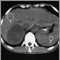

Pheochromocytoma is a rare tumor of the adrenal gland that causes too much release of epinephrine and norepinephrine -- hormones that regulate heart rate and blood pressure.

Pheochromocytoma may occur as a single tumor or as more than one growth. It usually develops in the center (medulla) of one or both adrenal glands. Sometimes this kind of tumor occurs outside the adrenal gland, usually somewhere else in the abdomen.